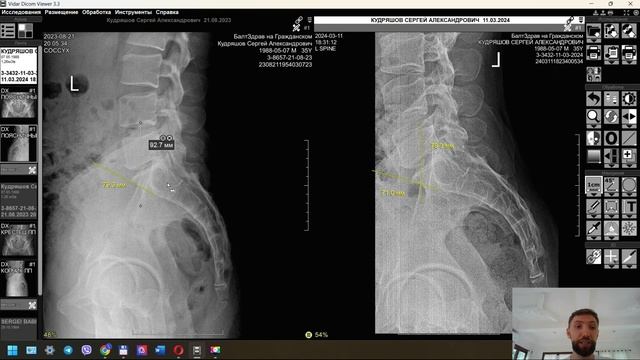

Полный разбор снимков до курса сеансов и через 6 месяцев после курса

Заметный результат после повторного осмотра